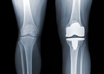

Knee replacement surgeries fell 40% in India due to COVID: Experts